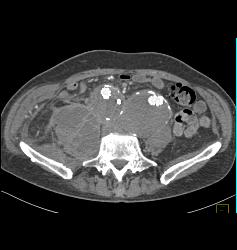

Diagnosis

Popliteal Artery With Disease in Trifurcation Vessels- See Full Sequence